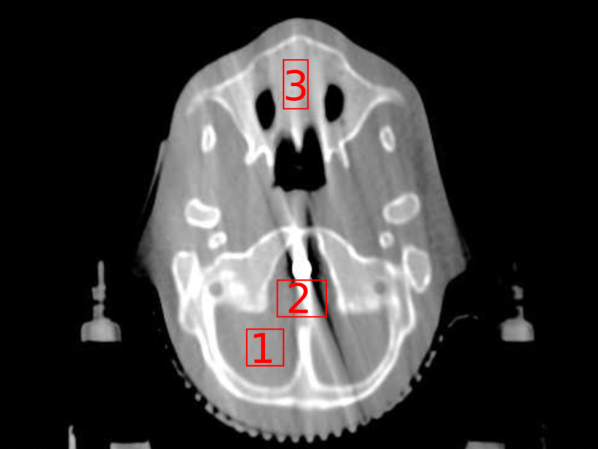

For reconstruction, we mapped into a resolution of 512×512×144512512144512\times 512\times 144, and used each method as detailed in Section 4.2.1. We ran each iterative method for 500 iterations. For the regularisation parameter, we heuristically used 0.5λpelvis0.5subscript𝜆pelvis0.5\lambda_{\textrm{pelvis}}, where λpelvissubscript𝜆pelvis\lambda_{\textrm{pelvis}} were the same TV regularisation parameters from the digital pelvis experiment, and gave good empirical performance on the CBCT data. Finally, for the bone and metal segmentations required for Poly-SIR, we obtained these through applying thresholds on the FBP and PWLS separately. To illustrate the critical role of this step, we have shown both images in Figures 11(c) and 11(d).

Refer to caption

(a) FBP CBCT

(b) PWLS CBCT

(c) Poly-SIR CBCT 1

(d) Poly-SIR CBCT 2

(e) IMPACT CBCT

(f) Polyquant CBCT

Figure 11: Results from electron density reconstruction from real CBCT data showing slice 83, where each is shown with display window [0.7,1.4]: (c) is Poly-SIR given a bone and metal segmentation derived from the FBP; (d) uses a segmentation derived from the PWLS

Reconstructions of the 83rd slice from the CBCT data are shown in Figure 11, along with a region from the 91st slice containing a higher mass of metal in Figure 12. Although the FBP appears to suffer strongly from the presence of the metal structure, most of the iterative methods mitigate its effect considerably, with the PWLS showing a more pronounce dark region in the soft tissue. The Poly-SIR based on a segmentation from the FBP does suffer from its streaking as shown in Figure 11(d). Although a better performance is achieved through segmenting from the PWLS as in Figure 11(d), this will have a considerably higher total computational cost; the Poly-SIR region in Figure 12(c) is based on this PWLS initialisation. The preservation of bone structure appears to be similar between all the iterative methods. The Polyquant method appears to have the smoothest regions around the metal implant, whilst maintaining the same level of structure in the bone and objects surrounding the phantom.

To evaluate the quantitative accuracy of each reconstruction, we isolated regions of interest (ROI) in the 83rd slice located in soft tissue and spongy bone — these are shown in Figure 11(a). The RMSE of these regions are calculated relative to the electron density of the soft tissue and bone equivalent resins, and shown in Table 4.